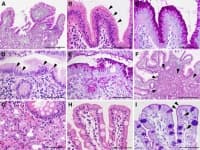

Метаплазия